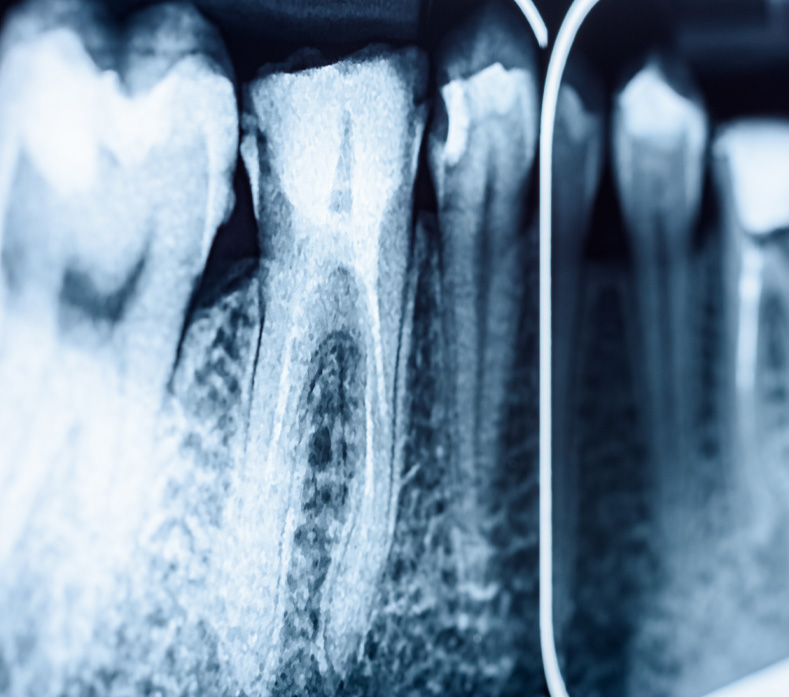

How do I know if I need a root canal?

Common signs include lingering toothache, sensitivity to heat or cold, swelling, or a darkened tooth. We’ll confirm with an X-ray and exam.